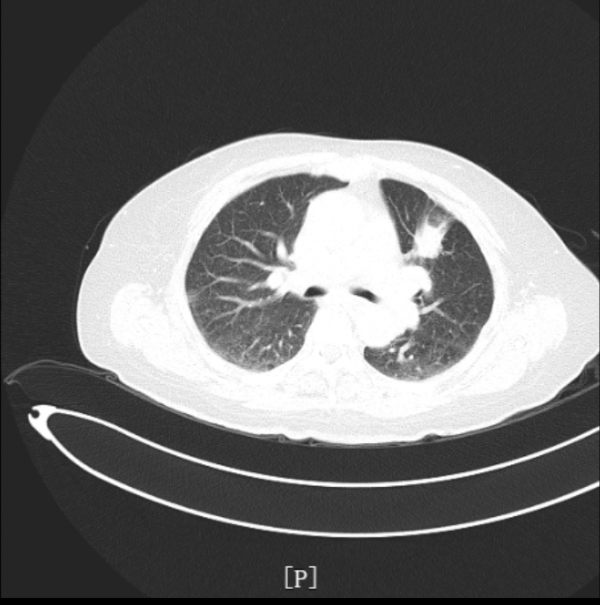

▎入院影像學檢查:

- 肺部CT檢查提示:左肺上葉前段佔位性病變,伴遠端阻塞性炎症及肺不張,考慮:周圍型肺癌可能性大。

治療後安排患者複查肺部CT,提示左肺腫瘤性病變較前明顯縮小。療效評估PR。

該患者2021年5月因“咳嗽咳痰伴發熱10余天”入院,完善肺部CT檢查提示:左肺上葉前段佔位性病變,伴遠端阻塞性炎症及肺不張,考慮:周圍型肺癌可能性大。頭部MRI檢查提示:雙側小腦半球點狀異常強化灶,考慮轉移瘤病灶。雙側大腦半球及小腦半球腦溝鑄型明顯異常強化,考慮肺癌軟腦膜轉移。腦膜轉移較腦實質腫瘤轉移少見,但肺癌腦膜轉移患者預後更差。患者在2021年6月進行支氣管鏡檢查,取腫瘤組織病理檢查也證實,其左肺上葉佔位系肺腺癌。入院診斷:左肺上葉肺腺癌伴腦轉移。分級:T2NxM1c IV期。

根據《CSCO 2021非小細胞肺癌診療指南》推薦,治療組給予患者培美曲塞二鈉化療+貝伐珠單抗全身治療。直至患者完成三個週期聯合治療後,複查胸部CT提示:左肺上葉腫瘤病灶較前明顯縮小。且治療期間不良反應經對症治療後迅速緩解,患者耐受性良好。